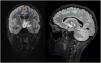

Se descarta edema de papila y se completa estudio con TC y RM cerebral (fig. 1). Por imagen se plantea, como principal sospecha diagnóstica, glioma difuso de línea media, sin poder descartarse patología inflamatoria. Por ello se completa estudio con RM con espectroscopia (RME), que no es concluyente para patología tumoral (fig. 2). Se retrasa biopsia quirúrgica y se solicita PET con metionina (no sugestiva de glioma de alto grado). Ante la sospecha de encefalitis autoinmune, se solicitan anticuerpos anti-MOG/AQP4 (negativos), y se inicia corticoterapia sistémica intravenosa1.